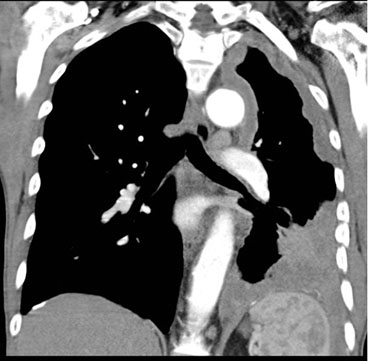

Mesotelioma: Es un tipo de cáncer poco común y de mal pronóstico, 63 que está fuertemente asociado en un 80% de los casos con antecedentes de exposición a fibras de amianto. Suele presentarse en pacientes de entre 50 y 70 años, 64 siendo más frecuente en hombres con una relación de 4:1. En la tomografía axial computarizada de tórax se puede observar un engrosamiento pleural circunferencial, nodular y con un espesor mayor a 1 cm. A menudo se asocia con derrame pleural unilateral y una disminución del volumen del hemitórax afectado. El diagnóstico se confirma mediante la obtención de tejido pleural a través de una biopsia, preferiblemente de naturaleza quirúrgica. 65-67

Tomografía computarizada (TC) de tórax: La TC de tórax es una técnica de imagen más precisa que puede mostrar con mayor detalle las alteraciones pleurales, como engrosamiento, calcificaciones, masas o derrame pleural (Figuras 4, 5 y 6).

El mesotelioma pleural es un tipo de cáncer que afecta el revestimiento delgado que rodea los pulmones y la cavidad torácica, conocido como mesotelio. El diagnóstico diferencial del mesotelioma pleural implica distinguirlo de otras enfermedades que pueden presentar síntomas similares (Figuras 7 y 8). Algunas de las condiciones que deben considerarse en el proceso de diagnóstico diferencial incluyen:

Pruebas de imagen: Se utilizan diversas pruebas de imagen para evaluar la presencia de anormalidades en la cavidad pleural. Estas pueden incluir radiografías de tórax con técnica OIT, tomografía computarizada (TC) de tórax, resonancia magnética (RM) y ecografía de tórax. Estas pruebas ayudan a detectar la presencia de derrame pleural, engrosamiento pleural, masas o nódulos en la pleura.

En resumen, se considera en estadio temprano una Radiografía de Tórax con técnica OIT (Organización Internacional del Trabajo), con lectura final que muestre cualquier anomalía pleural consistente con mesotelioma (leída) a lo menos por dos lectores certificados con en esta técnica. TAC de tórax de alta resolución sin contraste que confirme anomalía pleural consistente con mesotelioma. Historia Ocupacional (HO) para fibra de amianto: la valoración exhaustiva del sitio donde el trabajador está expuesto a fibras de amianto por el profesional higienista es fundamental, quien proveerá datos sobre tipo/cantidad de fibras de amianto, tiempo/ calidad de la protección colectiva y personal, altura geográfica y tiempo de exposición en días/semanas/años.